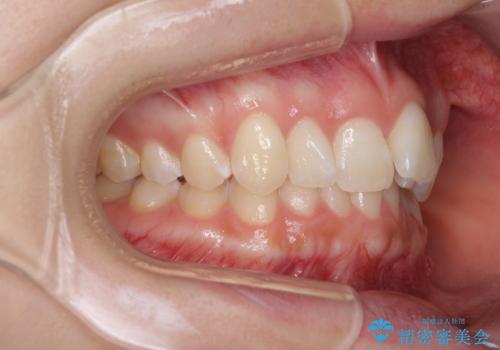

- 前歯のデコボコ気になるとのことで来院された患者様です。

下顎骨が上顎骨に対して右側にシフトしており、さらに下顎が後方に位置しているため、非常に強い咬合力で食いしばっている状態でした。

上下顎ともに歯列全体の後方移動とIPR(歯と歯の間を削る)によってデコボコが解消するように設計し、インビザラインにより治療を行うこととしました。

強い咬合力による臼歯部の噛みにくさと、それに伴う歯の移動の鈍さに悩まされ、非常に長い期間を要することとなりました。

上下正中位置は、治療開始時よりは改善したものの、ここが限界であろうというところでのゴールとなりました。

下顎前歯の大半が隠れている状態ですが、左右への歯ぎしりはスムーズに行うことができ、就寝時には後戻り防止も兼ねて、食いしばり対策としてマウスピースの使用を継続するようお願いしております。